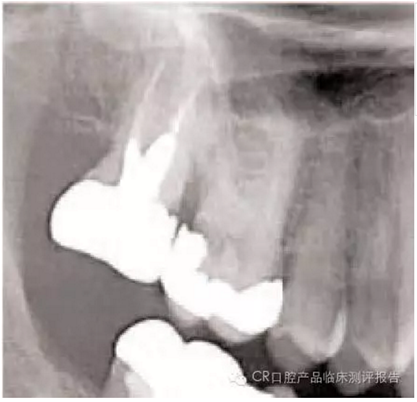

● 影像學(xué)檢查的要點

- 包括根尖:注意根尖的形狀(喇叭口、彎曲、融合、球形),有些情況需要牙根縱切。

- 找出牙根附近重要組織的影像:牙周膜(PDL)的缺口、上頜竇、血管神經(jīng)、高密度骨質(zhì)區(qū)域。根內(nèi)是否含有根管?(觀察比較難因為根管易碎或與骨長合)

病例

1. 最少顯露軟組織以方便牙挺(比如 301) 和牙鉗(150 或 53R)的放置,使用持續(xù)適當(dāng)力量的壓力。

2. 不要在遠中放牙挺,以防#2牙冠脫落。

3. 五分鐘左右還沒有進展的話, 切除#3略超出牙齦的冠部。如果可能,可以在分根之后,用小牙挺插入個別可以放入的牙根形成更快捷的入路。

4. 在不觸碰鄰牙的前提下,牙根不在上頜竇內(nèi)的情況下(需拍x線片確認,放置根間有竇腔),可以用702車針將復(fù)雜牙齒的腭根和頰根分開。